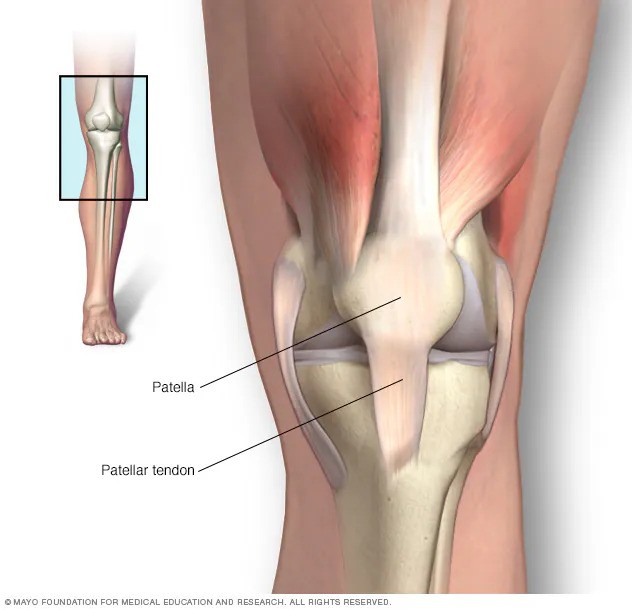

تاندونیت کشکک : تاندونیت کشکک آسیبی است به تاندون متصل کننده کاسه زانو (کشکک) به استخوان ساق پا. تاندون کشکک با عضلات جلوی ران شما کار می کند تا زانوی شما را دراز کند تا بتوانید لگد بزنید، بدوید و بپرید. تاندونیت کشکک که به عنوان زانوی جامپر نیز شناخته میشود، در ورزشکارانی که ورزشهایشان شامل پرشهای مکرر است – مانند بسکتبال و والیبال، شایعتر است. با این حال، حتی افرادی که در ورزش های پرش شرکت نمی کنند نیز می توانند به تاندونیت کشکک مبتلا شوند.

تاندونیت کشکک

تاندونیت کشکک باعث ایجاد درد در تاندون کشکک می شود که از کاسه زانو (کشکک) تا ساق پا (درشت نی) امتداد دارد.